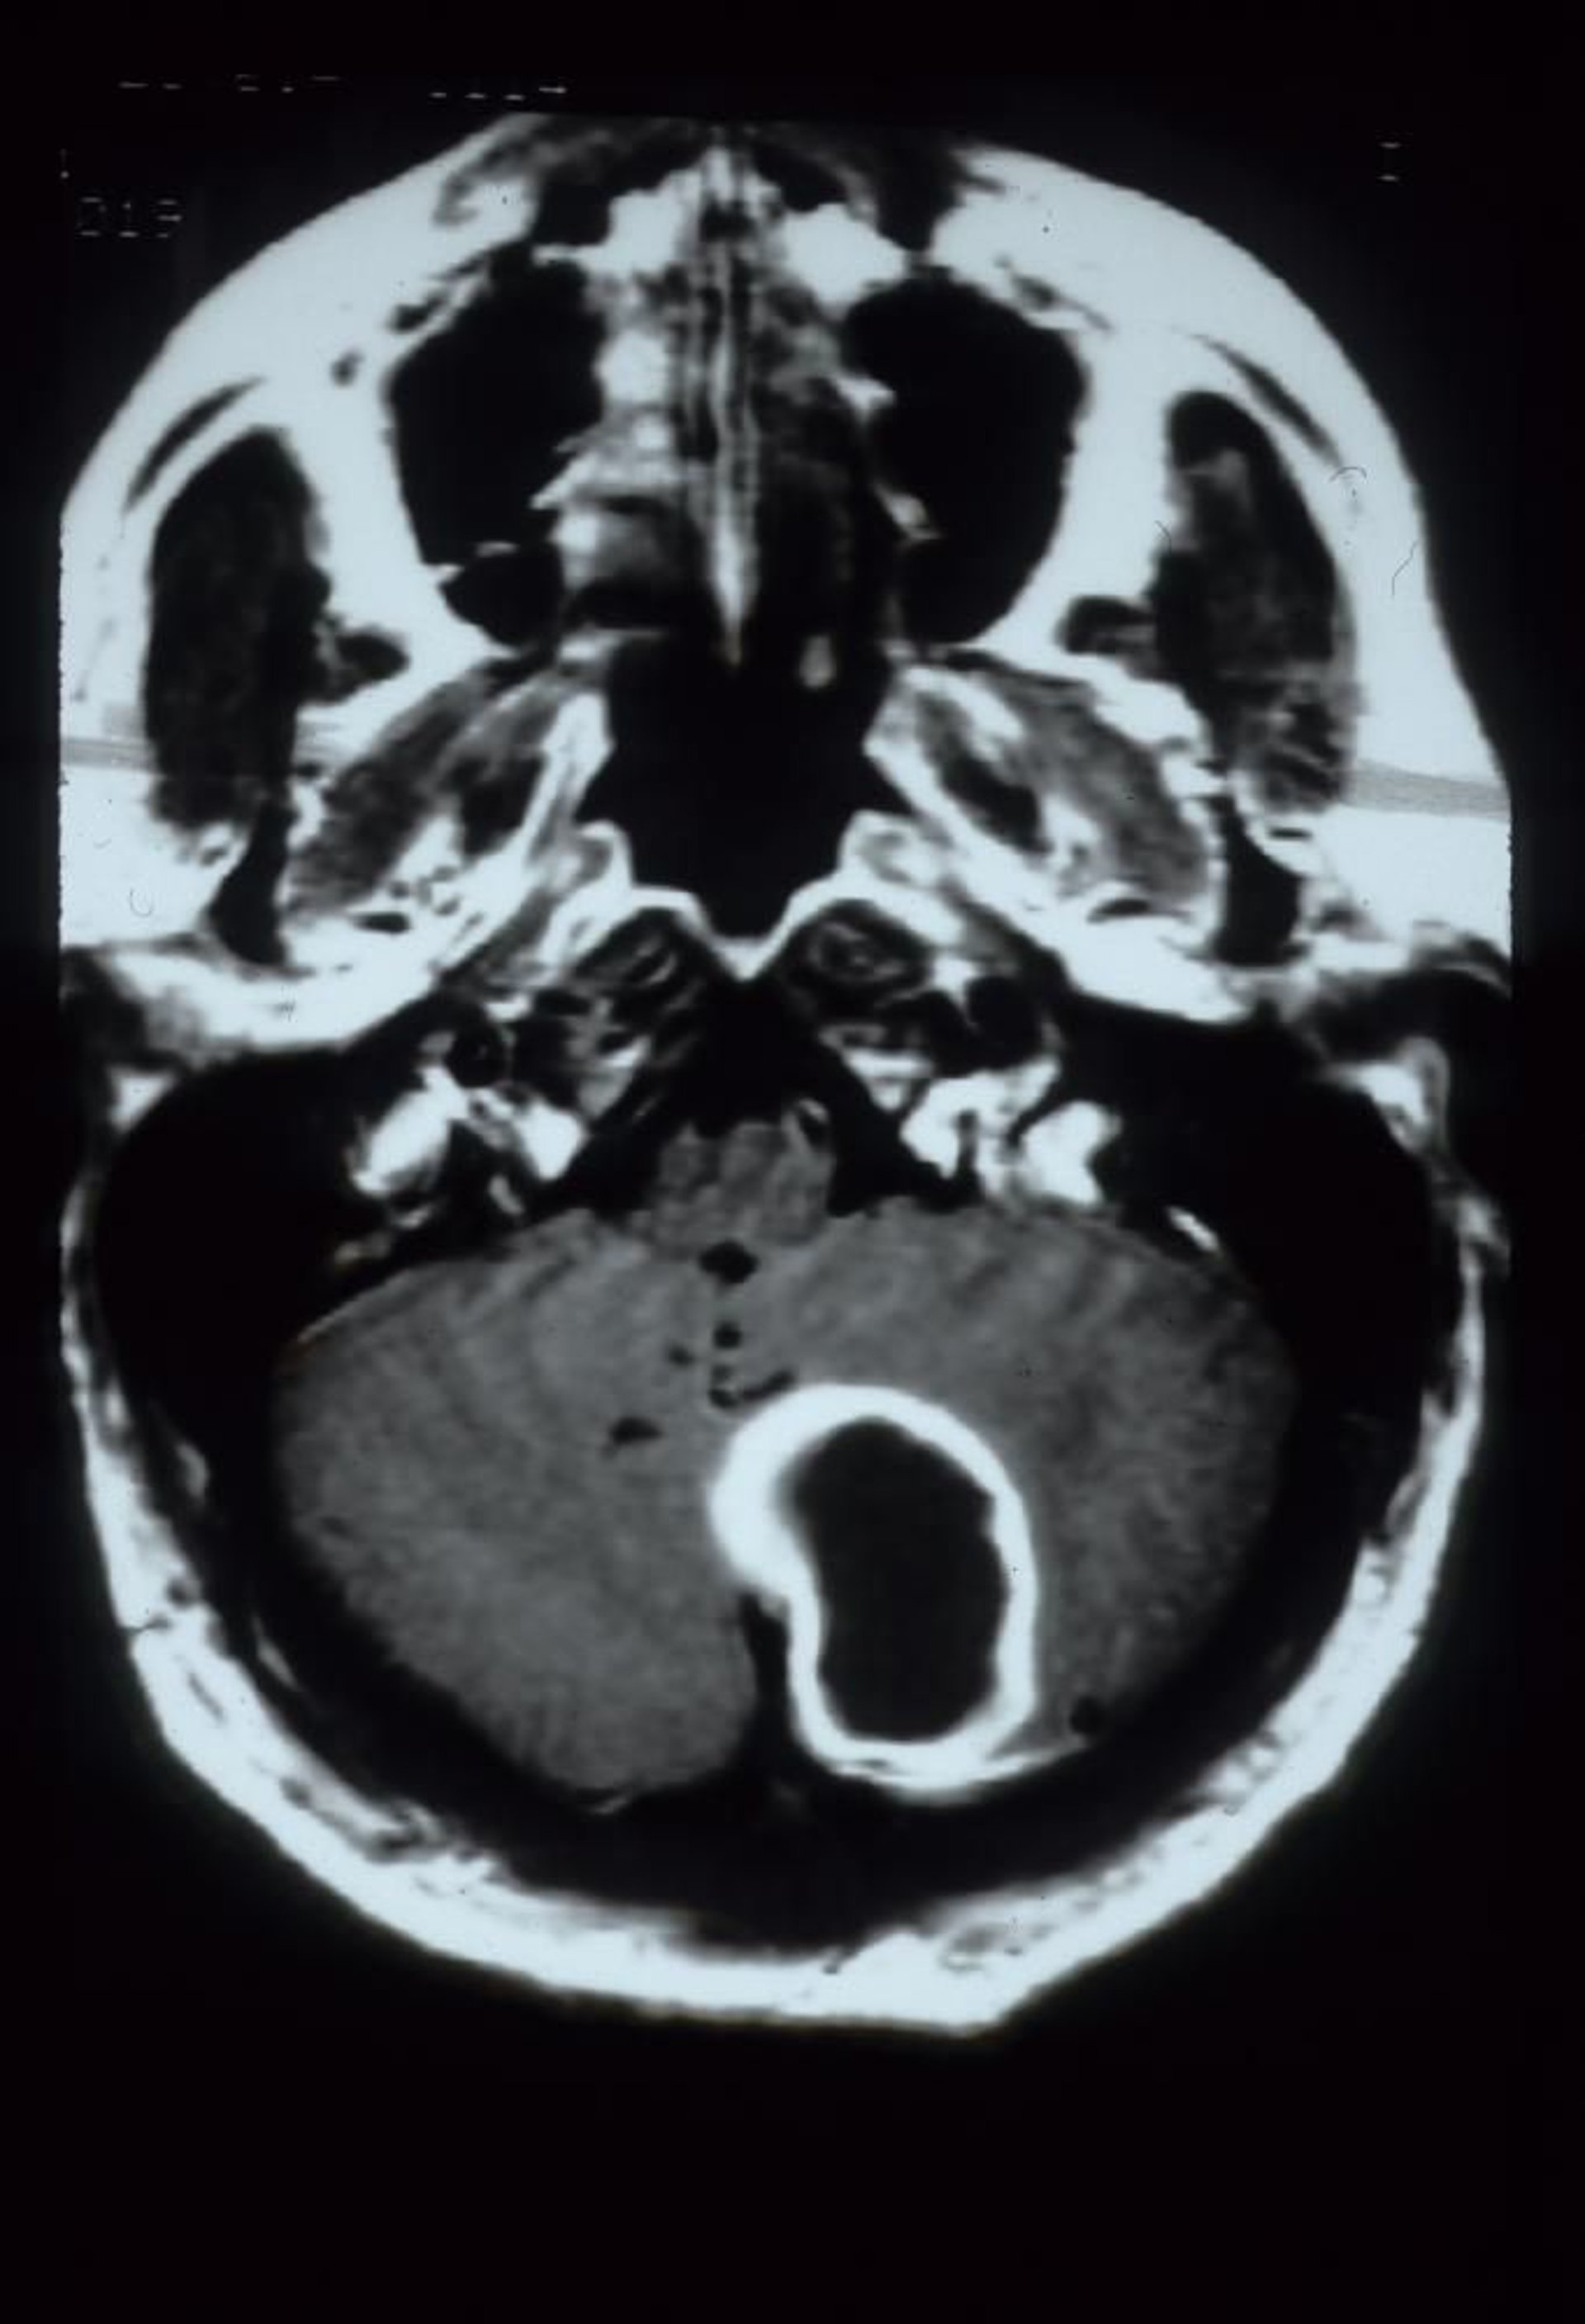

Quando i sintomi suggeriscono un ascesso, si effettua RM con mezzo di contrasto con immagini pesate in diffusione o, se la RM è non disponibile, TC con contrasto. Uno sviluppo completo dell'ascesso appare come una massa edematosa con un anello di ipercaptazione (enhancement) del mezzo di contrasto, che può essere difficile da distinguere da un tumore cerebrale o, più raramente, da un infarto; al fine diagnostico possono pertanto rendersi necessari un drenaggio TC-guidata, la coltura, l'escissione chirurgica o una combinazione dei precedenti.

Questa scansione RM potenziata con gadolinio mostra un ascesso cerebellare, che appare come una grande lesione cavitaria a bordi intensi nell'emisfero cerebellare sinistro.

Courtesy of John E. Greenlee, MD.